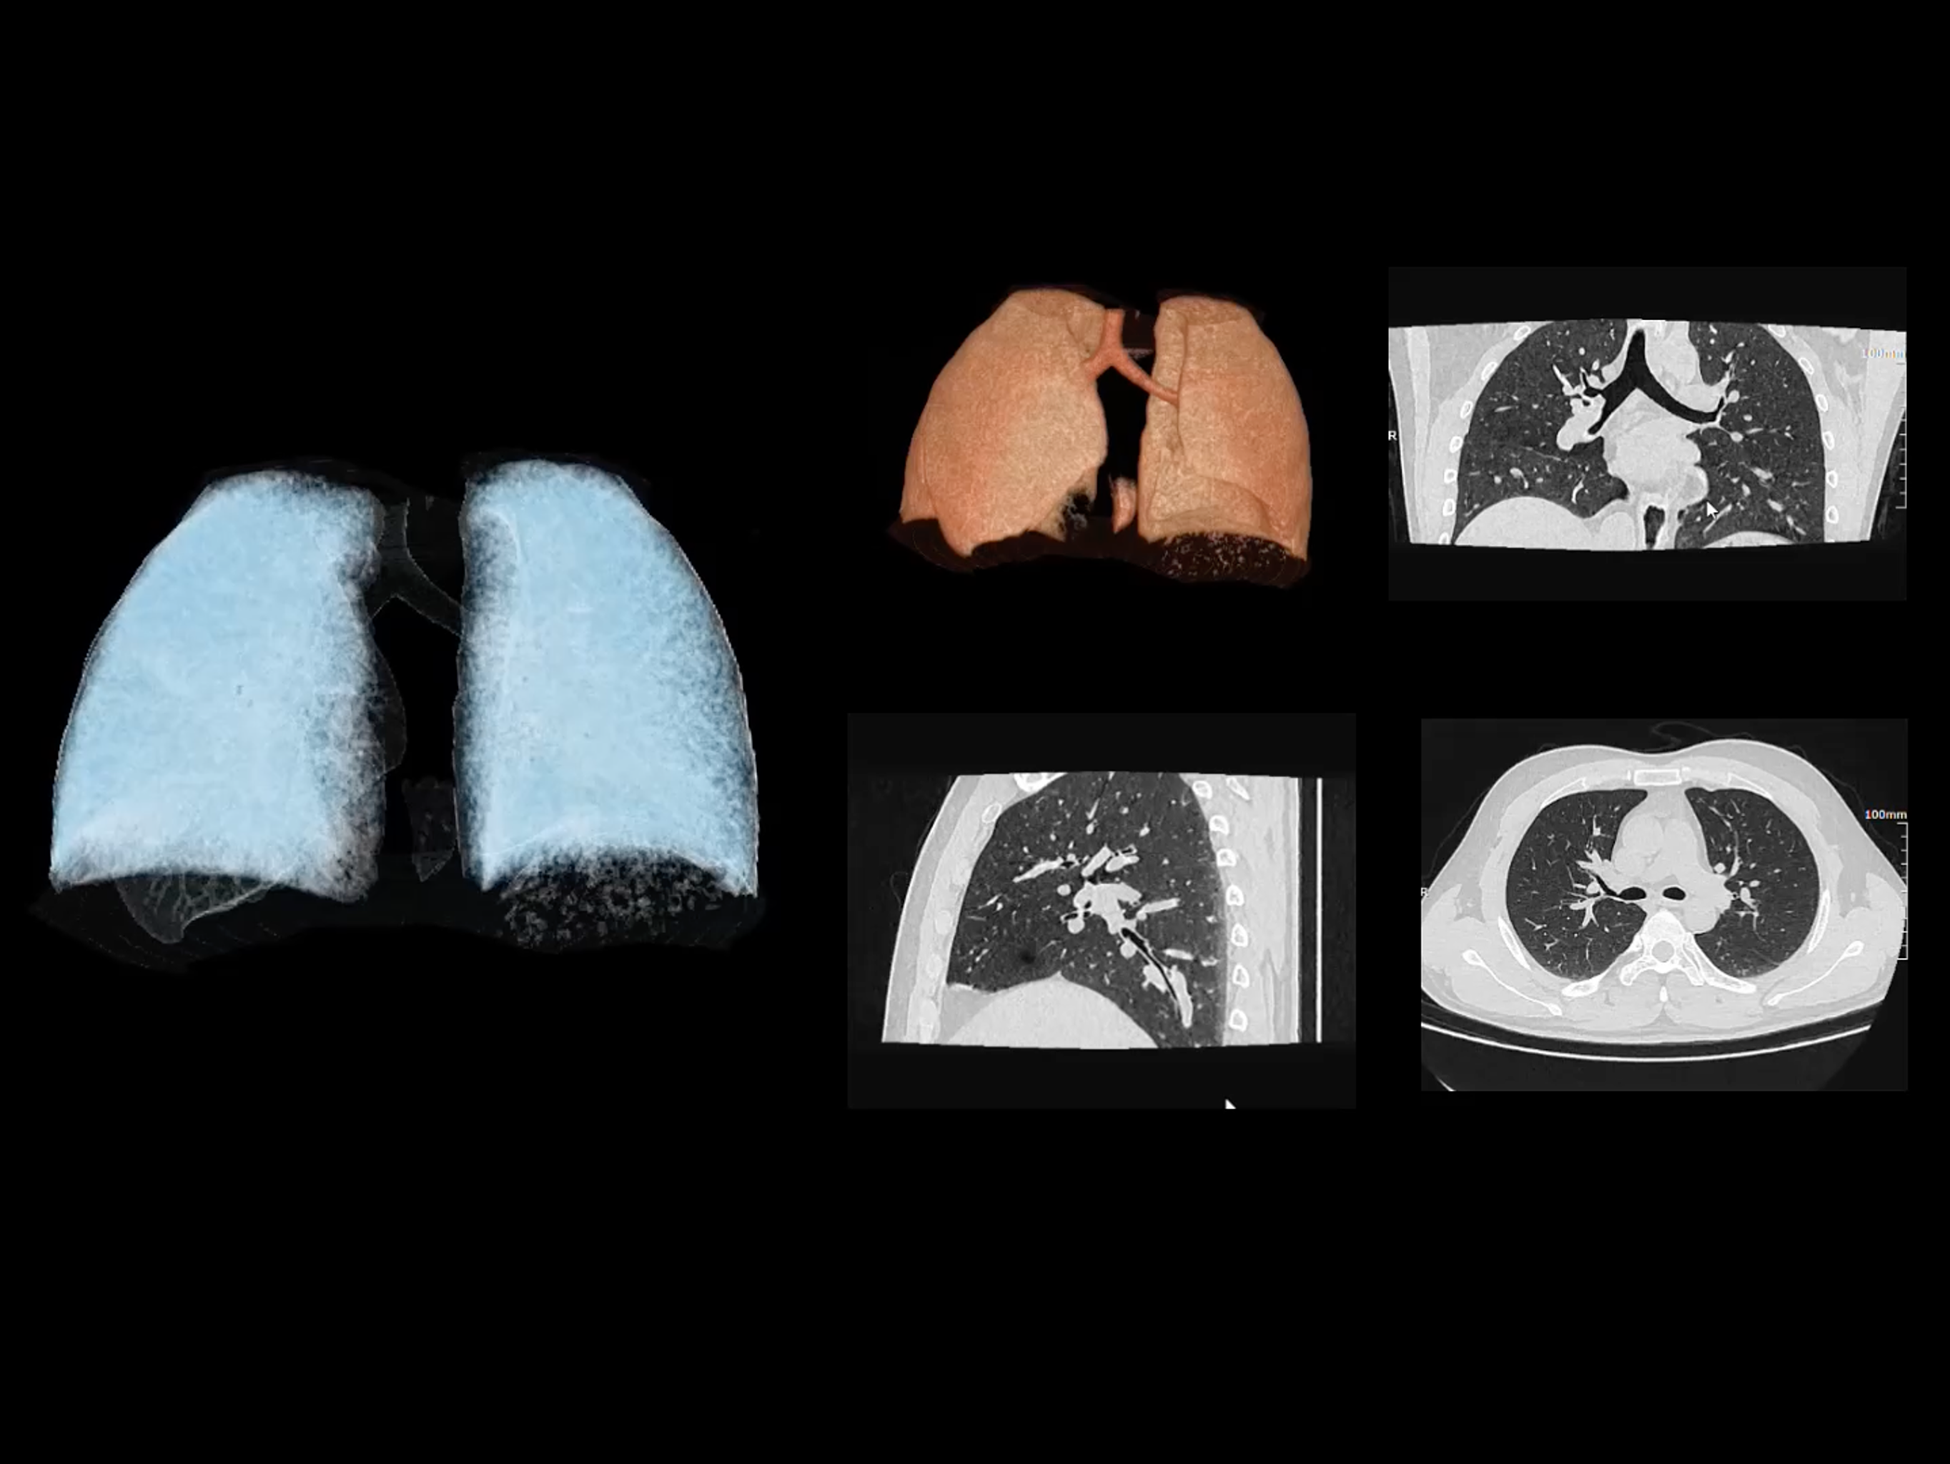

全身运动

uCT SiriuX® 以全新双宽体系统架构,同步实现超高时间分辨率与宽体容积覆盖兼得,全面释放性能潜能,敏锐捕捉人体生理运动全景,带来动态影像新视角。

巅峰系统形态

双宽体“零”噪声时空探测器,Z 方向覆盖达16 cm,单圈即可完整扫描头颅、心脏等关键器官,结合超高时间分辨率,可实现真正意义上的全身各部位高清动态成像,让每一次扫描都更高效、更精准。

uCT SiriuX® 以16cm超宽Z轴覆盖,使超高时间分辨率应用于完整器官成像。无论是心脏搏动还是关节运动,整个目标区域可在同一瞬时被完整、清晰地捕捉,彻底消除时序误差,实现从“局部瞬间”到“全器官瞬时”的成像跨越。

全身各部位动态CT成像